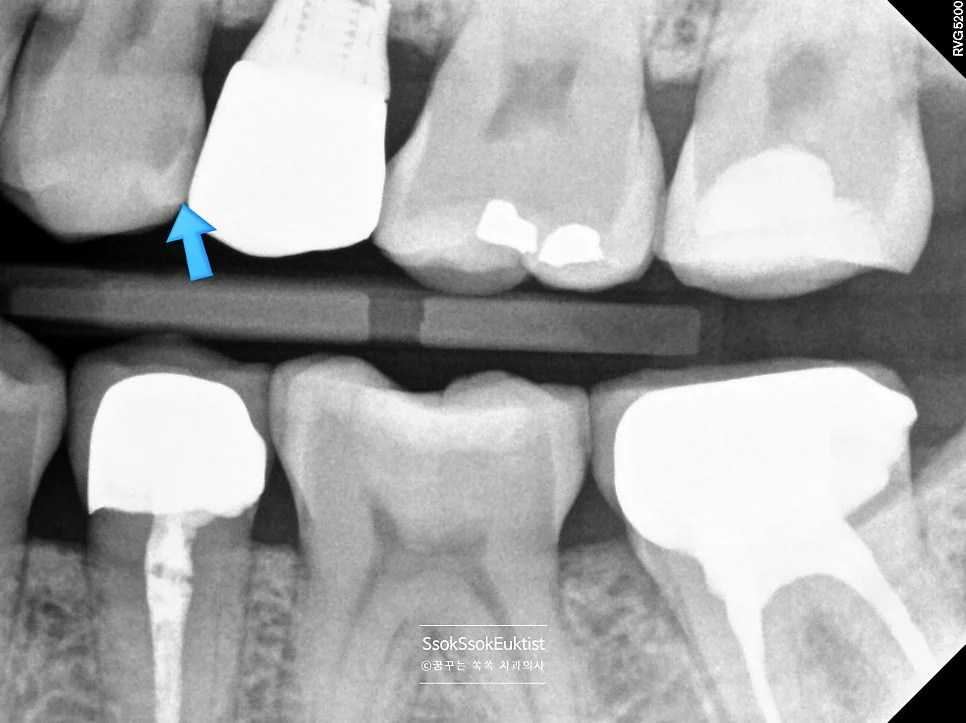

5번 치아 — 임플란트 인접 충치

5번 치아 — 임플란트 바로 앞 치아의 충치

5번 치아의 경우 임플란트 바로 앞 치아인데요.

임플란트는 움직이지 않는 데 반해 다른 치아는 평생에 걸쳐 가운데로 몰리는 경향이 있어 임플란트의 바로 앞 부분은 시간이 지나면 틈이 생기고 음식물이 잘 끼며, 이것이 방치될 경우 충치로 발전할 수 있습니다.